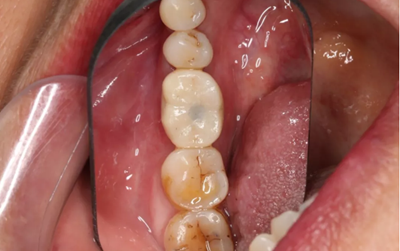

18、最終修復(fù)(口腔照片)

常規(guī)制作全瓷冠,試戴合適,粘接固位。

(攝于2018年6月13日)